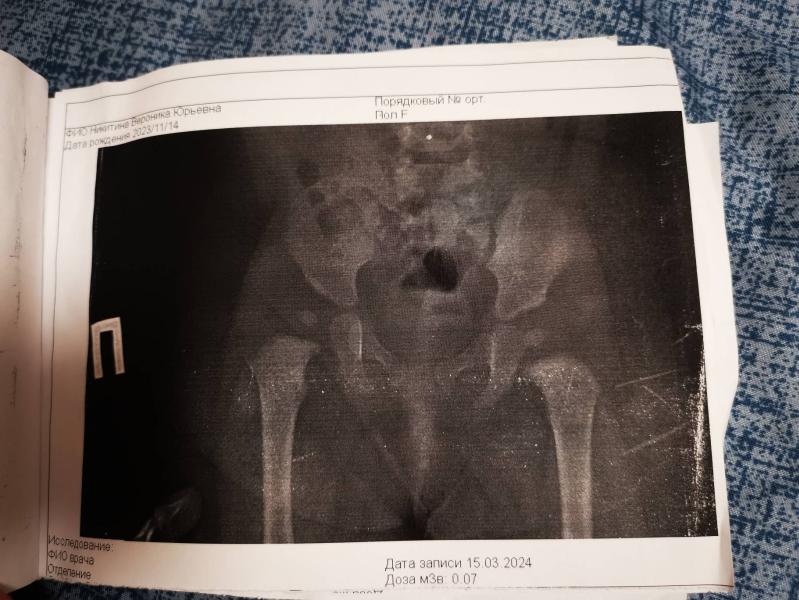

Прикрепила документы. Массажистка сказала, мы сходили на приём к травматолог, попросили рентген. На узи в 1 месяц все норма, и по описанию рентгена все хорошо, но на снимке видно, что она кость выше другой и по ножкам это заметно.